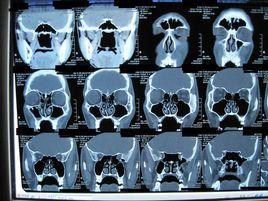

鼻竇冠位平掃

鼻竇冠位平掃 - 部位 鼻腔和鼻竇由軟組織和骨組成,腔道內含有氣體,最適用CT檢查。CT能發現其微小的病變,確定病變的部位和範圍;CT還可兼顧顯示軟組織和骨骼,發現液平、鈣化、壞死性病變,區分腫瘤性病變與炎症性病變。